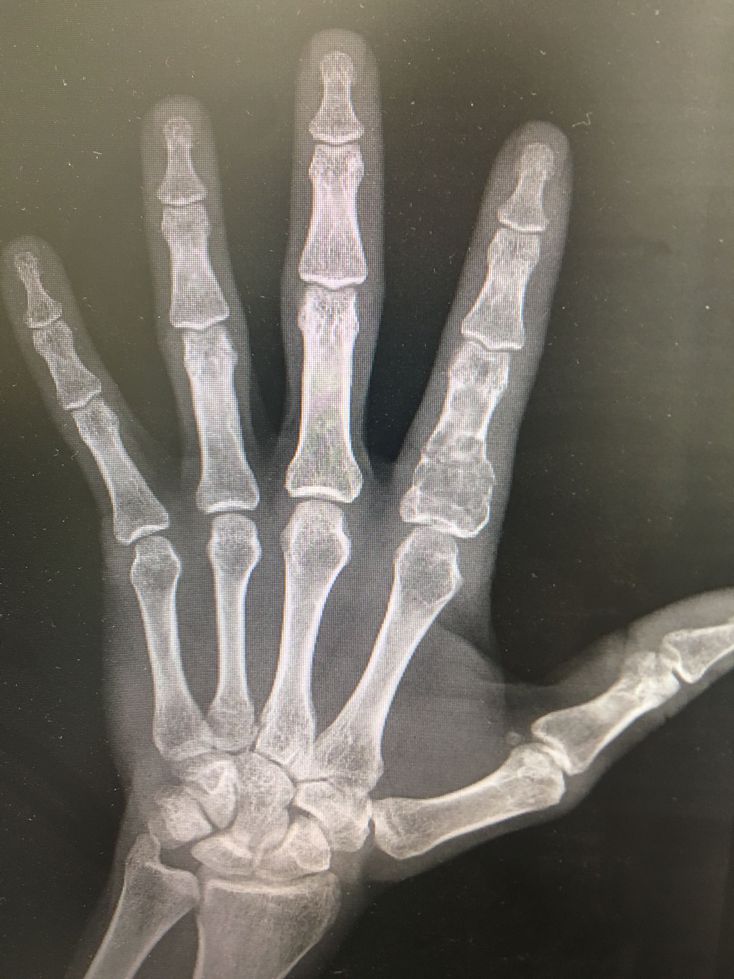

Patient came toE.R .see fracture in proximal phalanx the image take after 20days ,after remove the splint !

RA